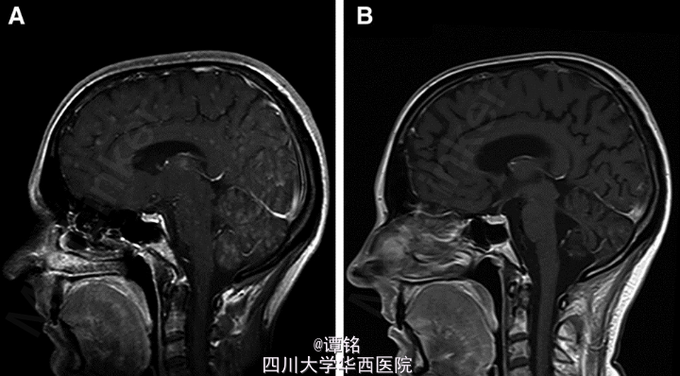

弥漫性脑转移的诊断表现为病灶在 T1 加权像增强 ( 图 3A)。暂停使用克唑替尼,患者接受 10 次 30Gy 剂量全脑照射 (WBRT),然后继续使用克唑替尼。 全脑照射显著改善了患者症状,治愈了抑郁,仅存在轻微的发音困难。全脑照射 4 个月后,增强 MRI,TI 加权像表现为脑内病灶的部分缓解 ( 图 3B),而 CT 表现为胸部病灶的进一步的缩小 (图 1C)。